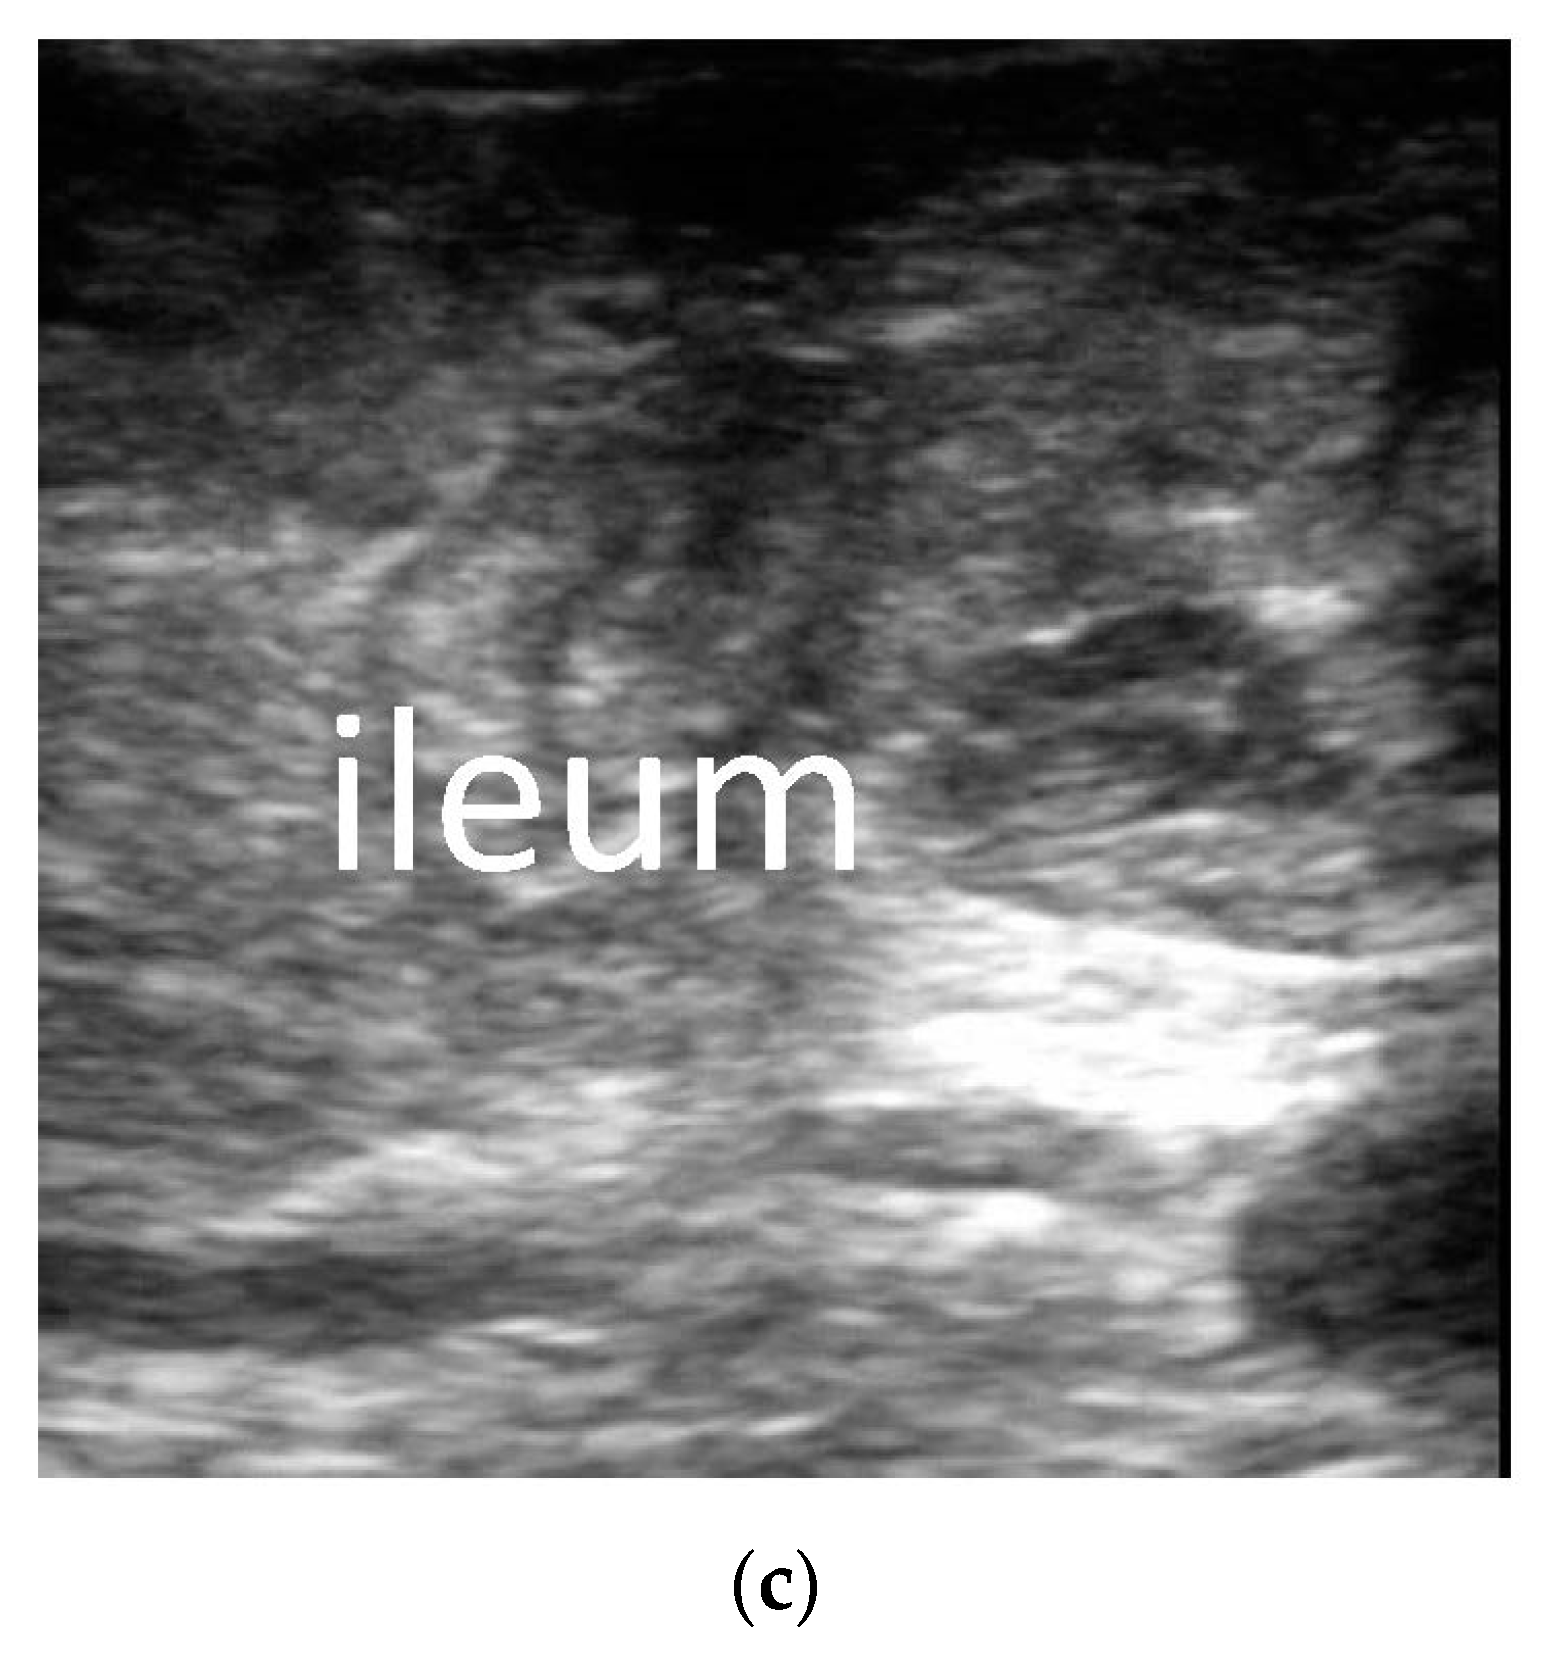

3.2. The Ultrasonic Manifestations

3.2.2. The Corresponding Ultrasound Findings of Diseases Leading to Neonatal Ileus